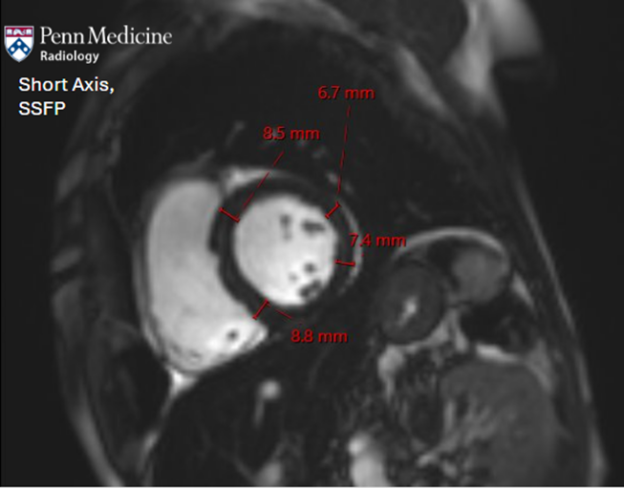

38-year-old man with thalassemia and fatigue

A 38-year-old man with a history of thalassemia and history of multiple blood transfusions presented with fatigue.